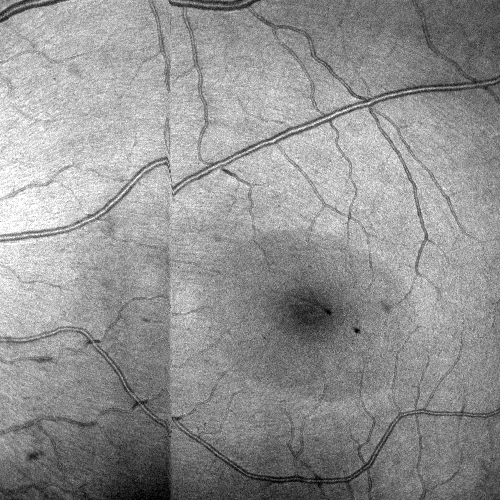

Images and estimated displacements are shown for a representative scan in Figureย 3. Tiny discontinuities prove absence of overregularization, and consistent transverse vibration indicates partial correction of ocular tremor. For quantitative analysis, we computed the median distance between the aligned A-scan displacements, and the fraction of displacements with a distance above 0.5 (problematic for supersampling) and 1 pixels (misalignments). The first and last 5% of B-scans were excluded, because they might not overlap with the orthogonal data, preventing registration. As the distributions are heavily skewed, we present box plots in Figureย 4. The three outliers in each direction in the right plot originate from the same subject, which is shown in supplementary Figureย 6. It is critical to note that the parameter density (B-scan rate 205 Hz) of the hermite splines is insufficient to fully correct ocular tremor (frequency up to 100 Hzย [16]). Therefore, this aperiodic, wave-like motion (amplitude 30โฒโฒ 1.6ย ยตm on the retinaย [16]) cannot be fully corrected, and neither is fully represented in the reproducibility error. In the transverse directions, this puts a lower accuracy limit on the evaluation scheme, but it is small compared to the pixel spacing (12ย ยตm). Using an Nvidia RTX 5000 GPU, the median and maximum runtime in the test set, excluding disk I/O which is irrelevant in clinical routine, was 8.6ย s and 31.3ย s. Tableย 1 compares average runtimes of various methods. Lastly, registration of individual B-scan repeats is demonstrated on a swept-source scanner in Figureย 5.